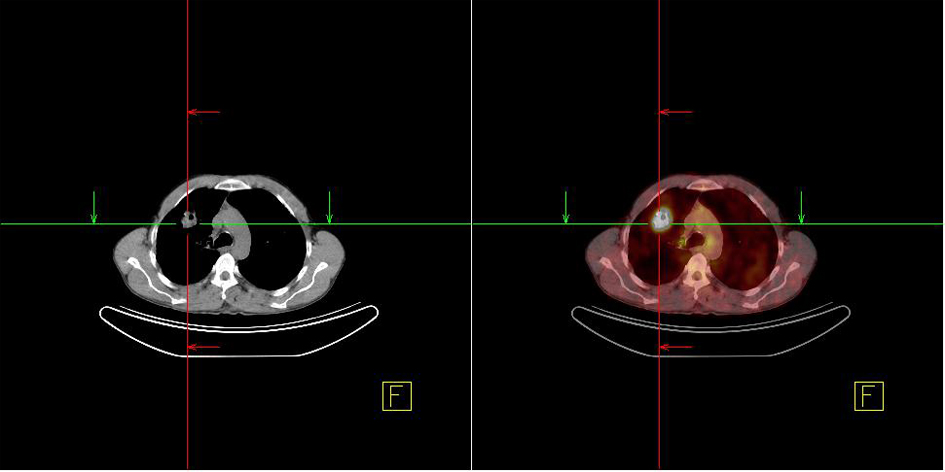

A 48-year-old male patient presented to the urology clinic for painless swelling of his right testis that has been going on approximately for two months. The patient had 60 pack/years of smoking history, and considering presence of a primary testicular tumor, he was scheduled for a surgery by the urology department. His pre-operative B-HCG and AFP levels were assessed, and found within acceptable limits, and he underwent orchiectomy. The immunohistochemical staining performed for the patient, who had a manifestation consistent with squamous cell cancer during the pathological assessment showed focal CK19 and keratin positivity as well as PLAP, AFP, CD30, CK5/6, HMWCK, TTF-1, HMB45 AND Melanin A negativity (Fig. 1 and 2). After the histological subtype was identified as squamous cell carcinoma, PET/CT imaging that was performed to detect the primary disease revealed a 3.5 cm malignant tumor in the right lung with an SUVmax of 9, metastatic nodules in bilateral lungs with an SUVmax of 2.6, and bone metastases in the right supraclavicular, upper right paratracheal, aorticopulmonary, subcarineal and left hiler lymph nodes with an SUVmax of 13, in the right surrenal gland with an SUVmax of 9.4, and in the lumbar vertebrae and left iliac bone with an SUVmax of 4 (Fig. 3). Considering squamous cell carcinoma of the lung as a primary focus, a palliative treatment was initiated with Gemzar (1,000 mg/m2, on day 1 and day 8, every 3 weeks), Cisplatin (75 mg/m2, on day 1, every 3 weeks), and zoledronic acid (4 mg/day, every 3 weeks).

![]() Click for large image | Figure 3. Lung mass detected in the PET/CT imaging. |